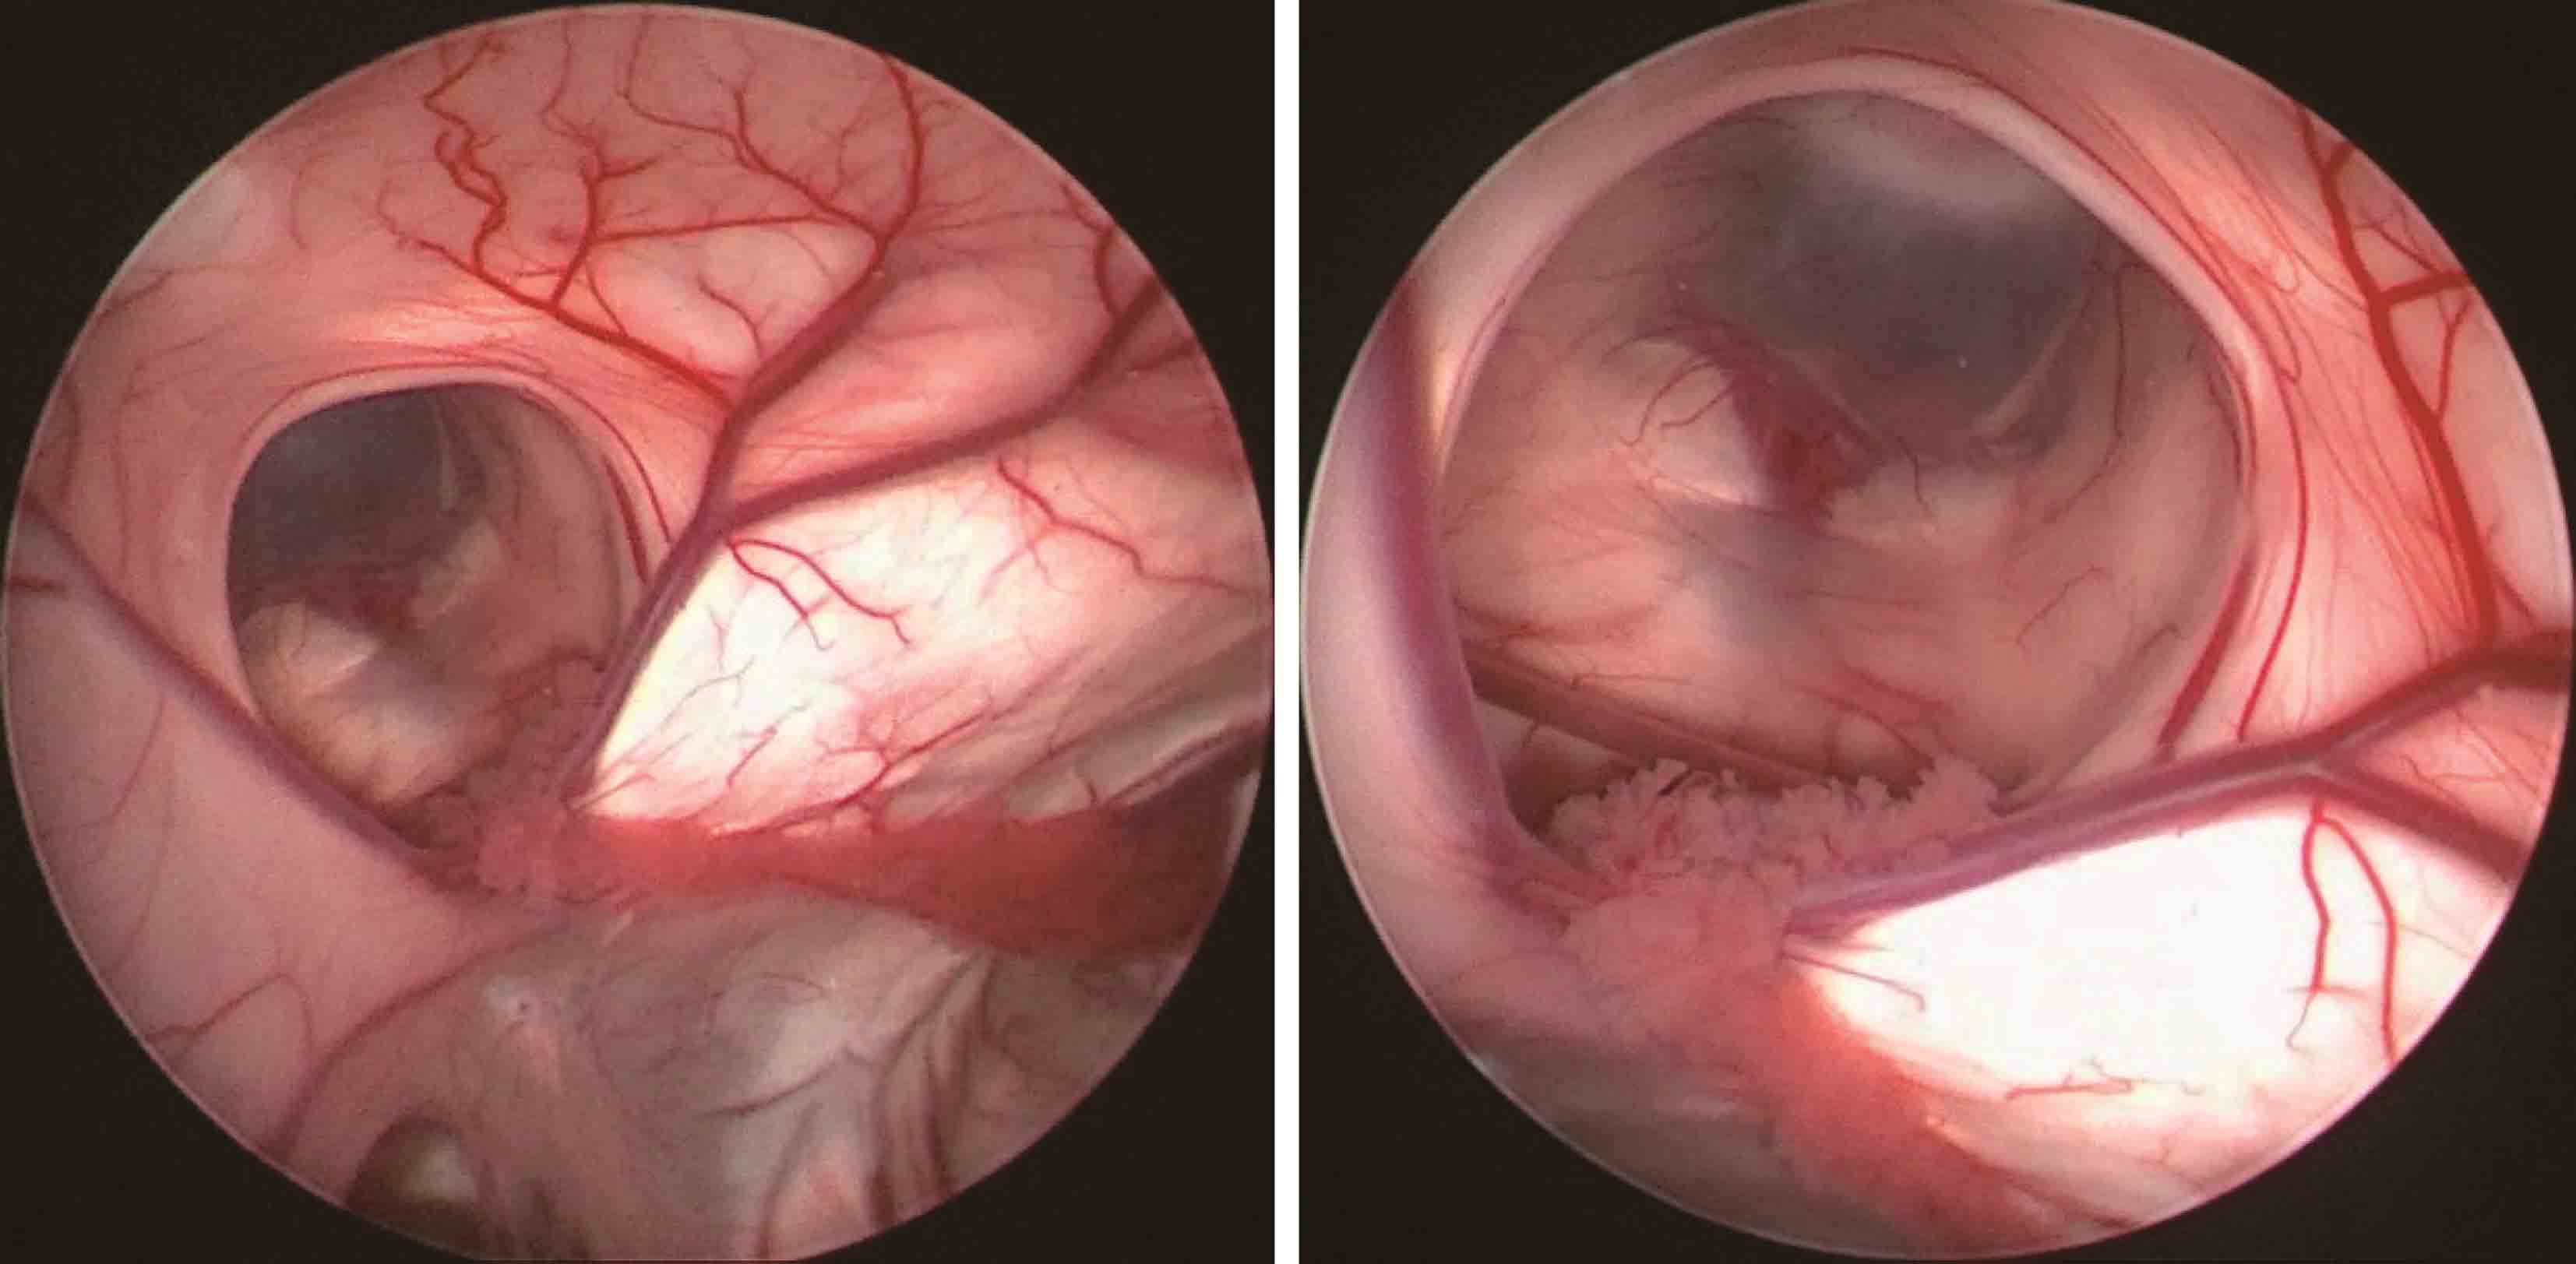

2.单侧或双侧室间孔狭窄或闭塞所致一侧或双侧侧脑室积水,采用内镜下室间孔成形术进行治疗(图3-1-2-1)。

图3-1-2-1 室间孔狭窄的影像学表现

a.右侧室间孔狭窄,头颅MRI轴位;b.右侧室间孔狭窄,头颅MRI冠状位;c.左侧室间孔狭窄,头颅MRI轴位;d.双侧室间孔狭窄,头颅MRI冠状位;e.内镜下可见左侧室间孔闭塞、右侧室间孔狭窄;f.内镜下可见左侧室间孔闭塞;g.内镜下可见右侧室间孔闭塞;h.室间孔球囊成形;i.经球囊成形后的室间孔